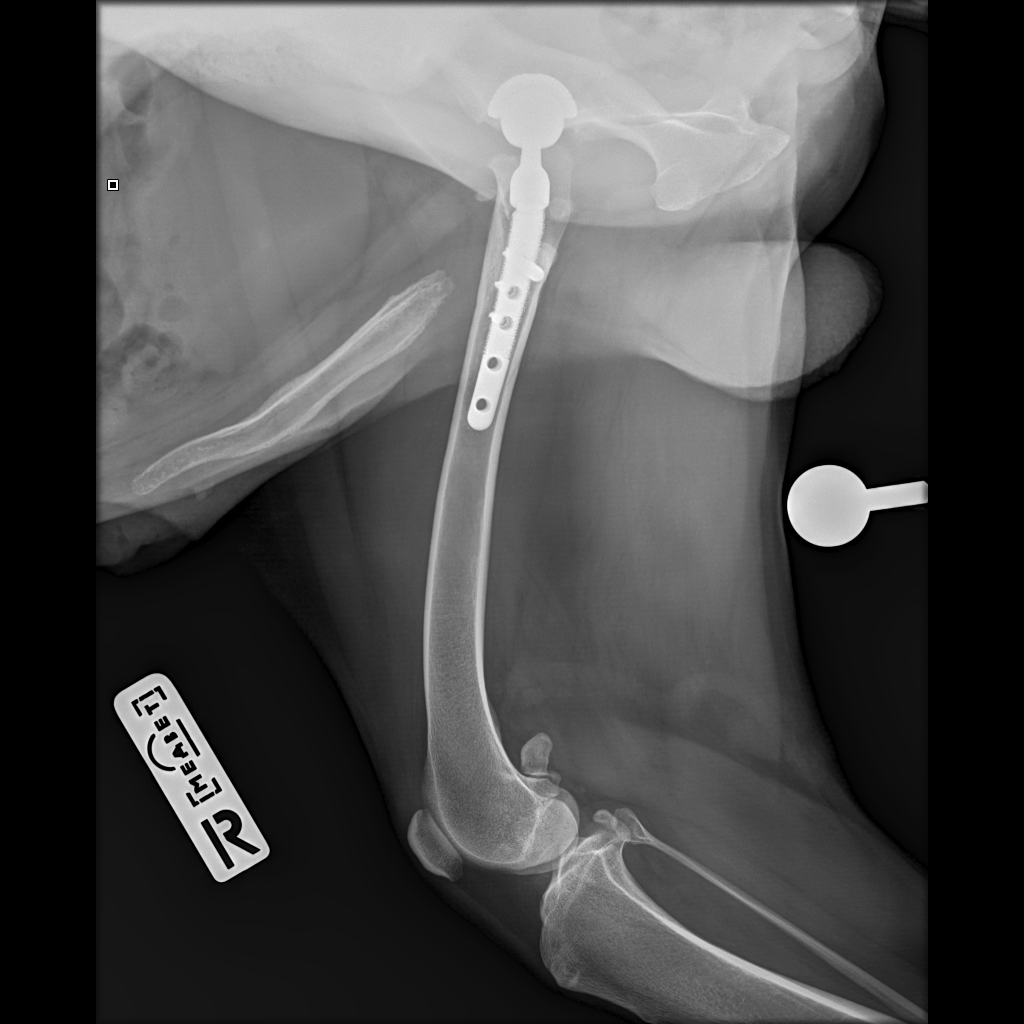

IMG-20221005-WA0005.jpg

IMG-20221005-WA0006.jpg

IMG-20221005-WA0007.jpg

8A836050-66CA-42B2-94D3-F13B288A592B.jpeg

39B2671E-39B9-4502-9E11-ADB169612F24.jpeg

6950B9C9-79EA-4F34-A780-9C3C6BA31B49.jpeg

58C20B18-AA4E-4386-BF83-56CE5E282844.jpeg

Наш металлический мальчик

Железный дровосек